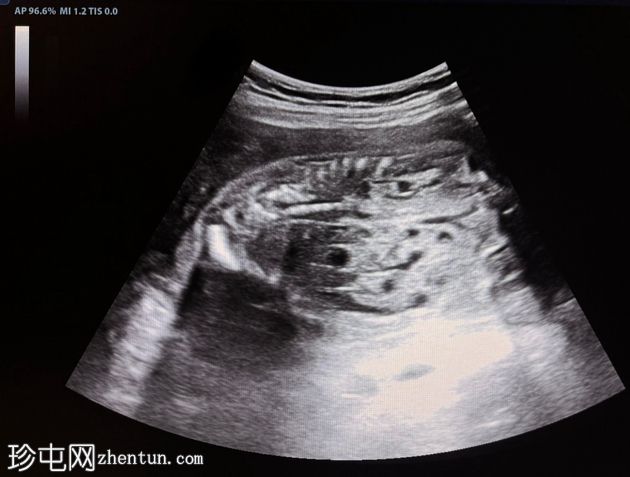

横切面

胎儿双肾增大,回声增强,伴多发性小实质囊肿

羊水过少,羊水指数(AFI)= 3cm(未显示)

上述特征符合常染色体隐性多囊肾病的诊断。